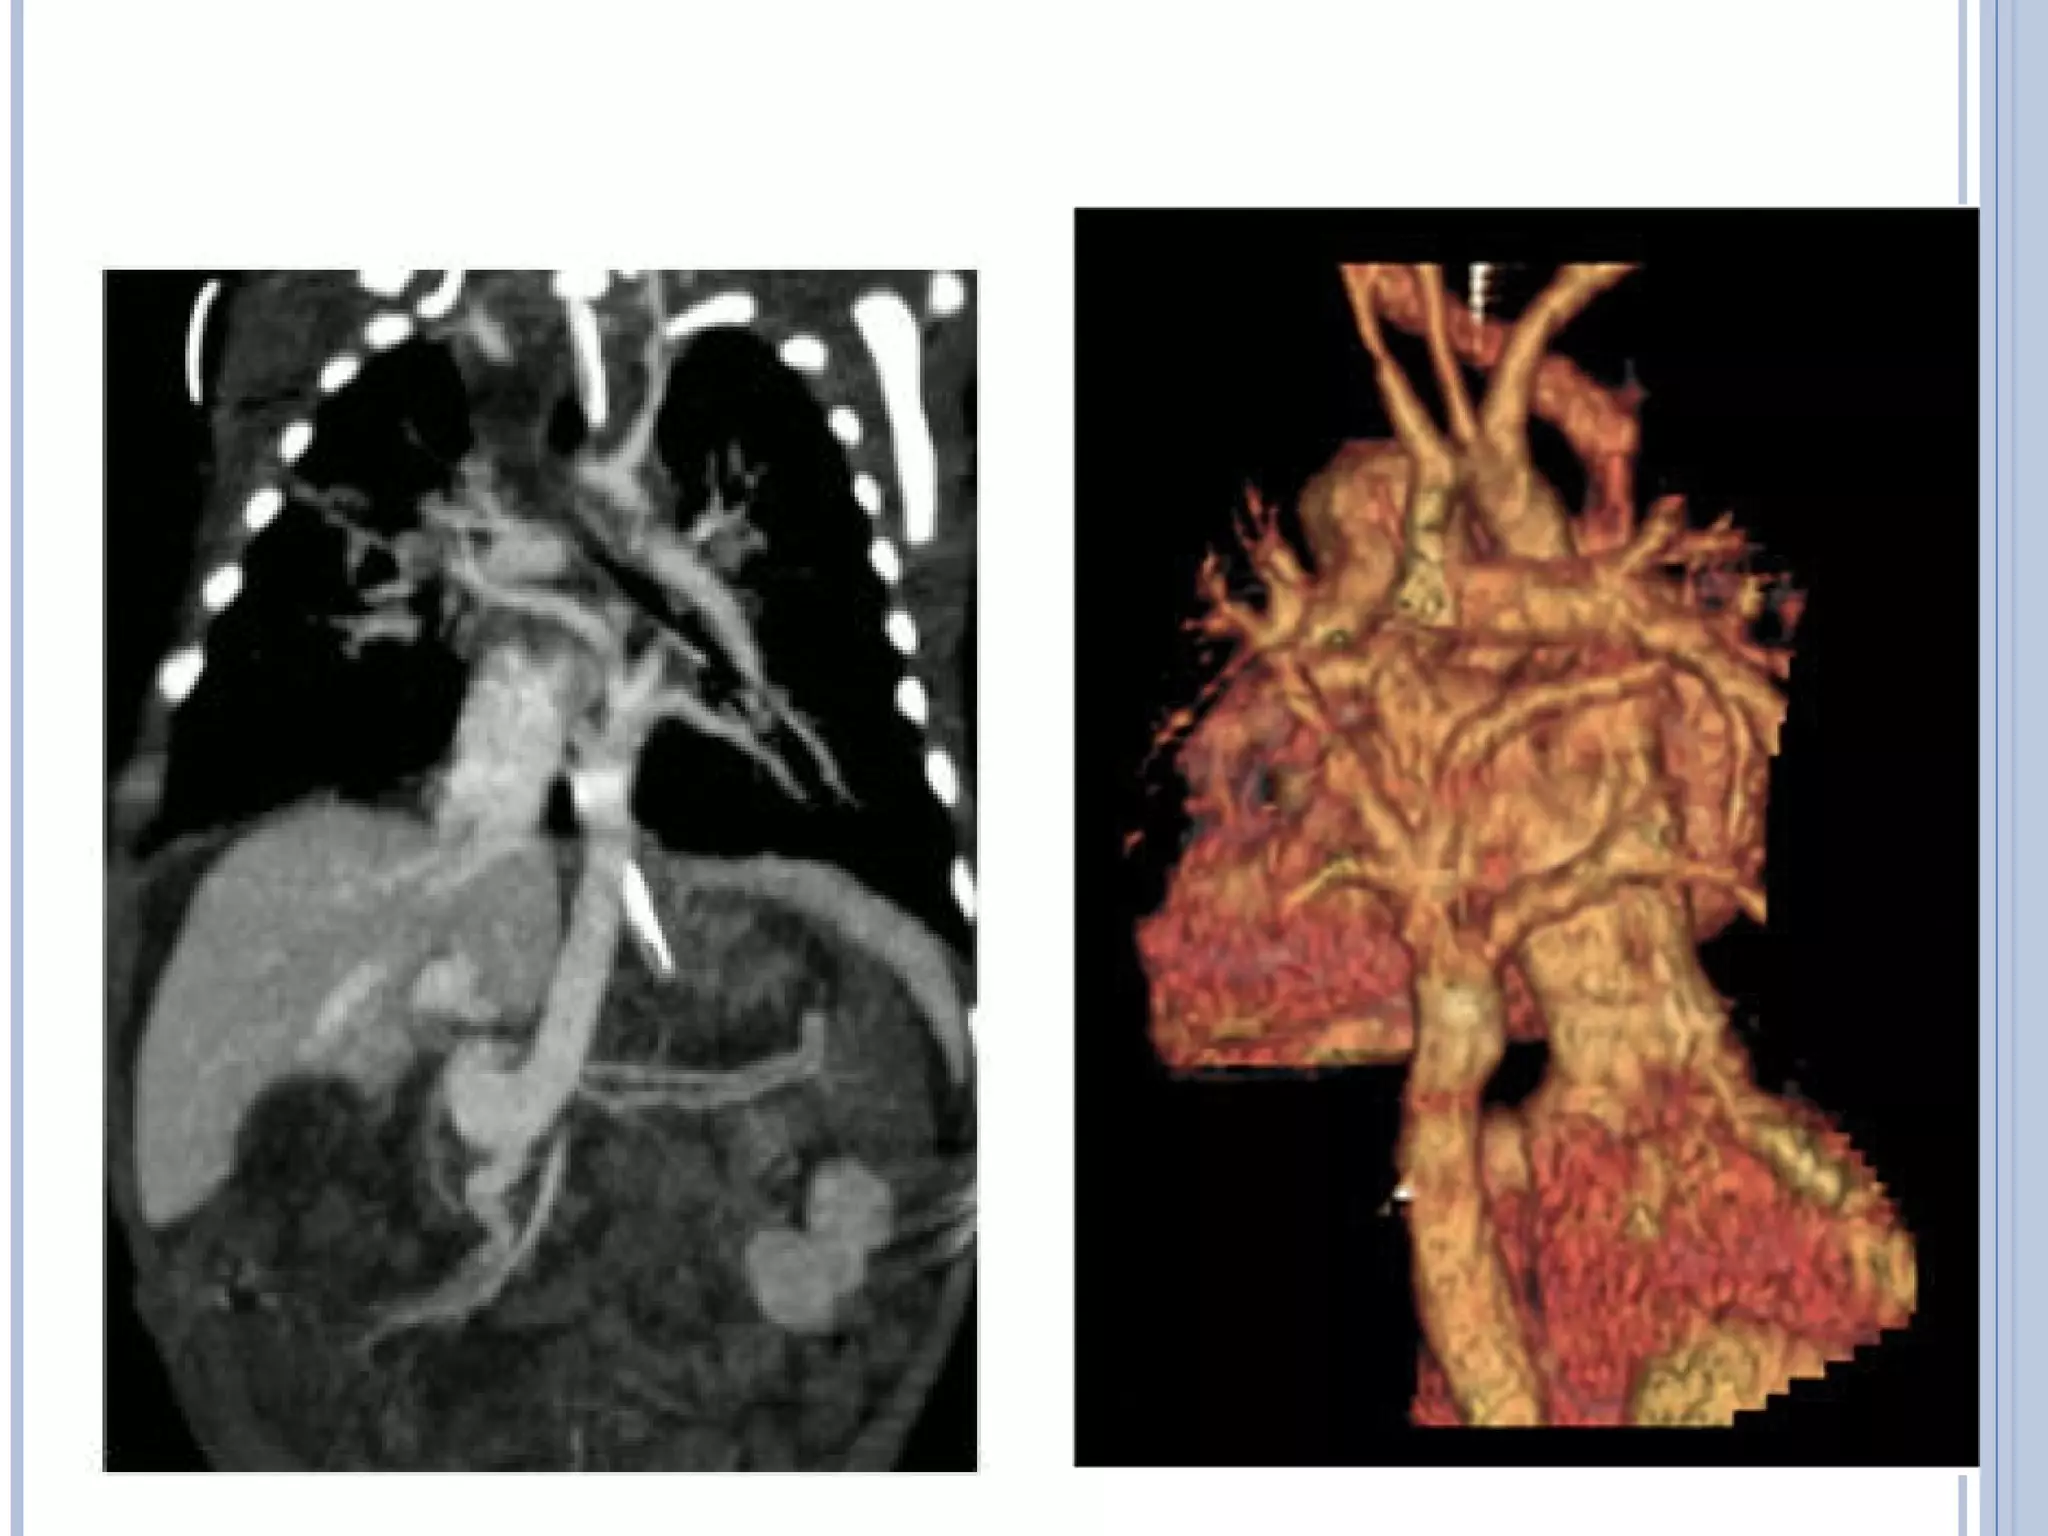

• #80 Angio CT examination with coronal MIP reformat and 3D reconstruction. Infradia­phragmatic type of total anomalous pulmonary venous connection. The four pulmonary veins join together and drain downwards, connecting to the liver&amp;apos;s portal vein system Angio CT examination. Infradiaphragmatic type of total anomalous pulmonary venous connection (reconstruction)